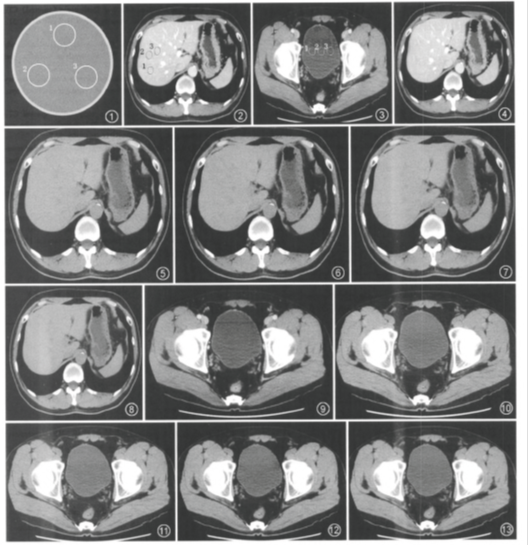

图1 质量评价标准体模水模部分CT值测量示意图,l、2、3为3个ROI。图2,3为能谱扫描65 keV单能量CT横断面图像,分别为肝脏(图2)和膀胱区(图3)实质测量示意图,1、2、3为3个ROI。图4—8为肝脏cT横断面图像。图4为能谱增强扫描65 keV单能量图像,图5为常规扫描滤波反投影(FBP)重建图像,图6~8分别为20%、40%和60%自适应统计迭代重建(ASIR)常规扫描图像,图5—8的图像噪声逐渐降低,图4的图像噪声与图7基本相当。图9—13为膀胱CT横断面图像。图9为能谱增强扫描65 keV单能量图像,图lO为常规扫描FBP重建图像,图11—13分别为20%、40%和60%ASIR常规扫描图像,从图10~13图像噪声逐渐降低,图9的图像噪声与图11基本相当。